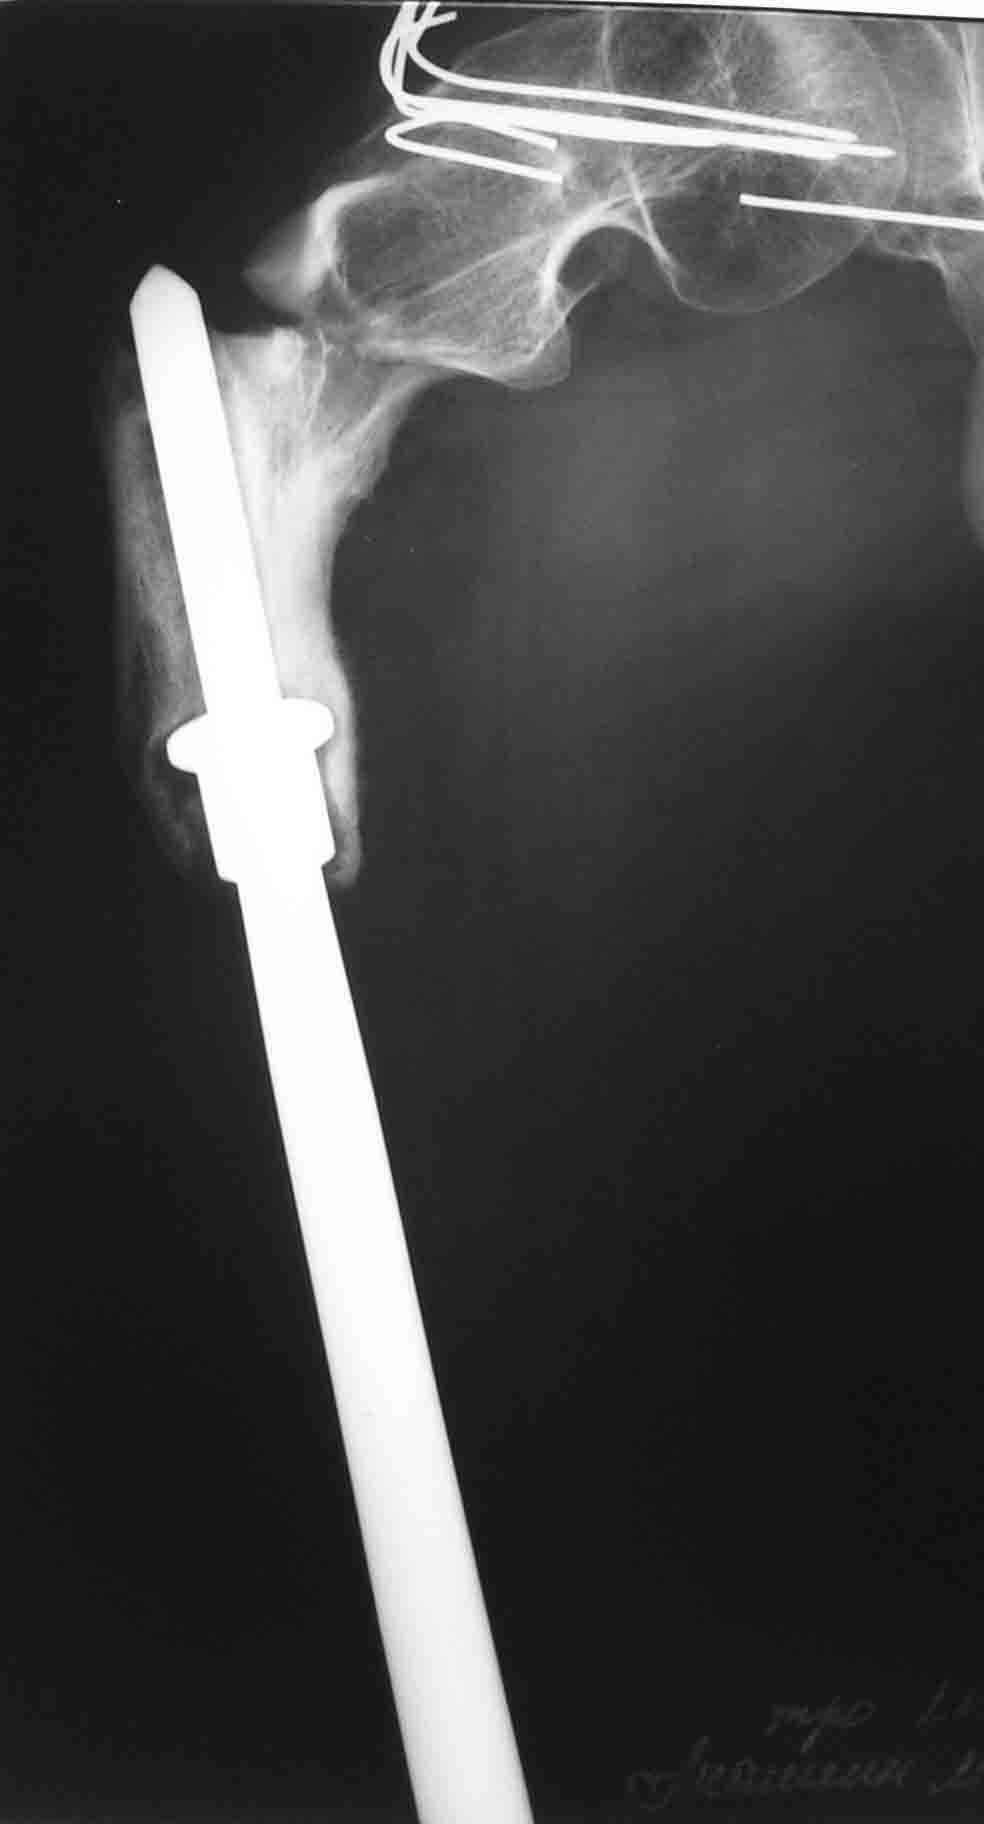

ГА> В марте этого года- повторный подвертельный перелом (см RG).

ГА> В настоящее время в коксите. Что дальше?

До травмы передвигался самостоятельно с дополнительной опорой (трость). Имеется укорочение ноги 15 см.

I would re-iterate suggestion for a fixed angle cable plate with cortical allograft struts around the prosthetic femur. Zimmer (and others) make them. The cables get purchase to the shaft by 1) go through horizontal slots in the plate or 2) onto grooves in the plate. The struts would be fixed by the cables too and keep the metal cables physically away from the metal prosthesis to minimize galvanic or fretting corrosion.